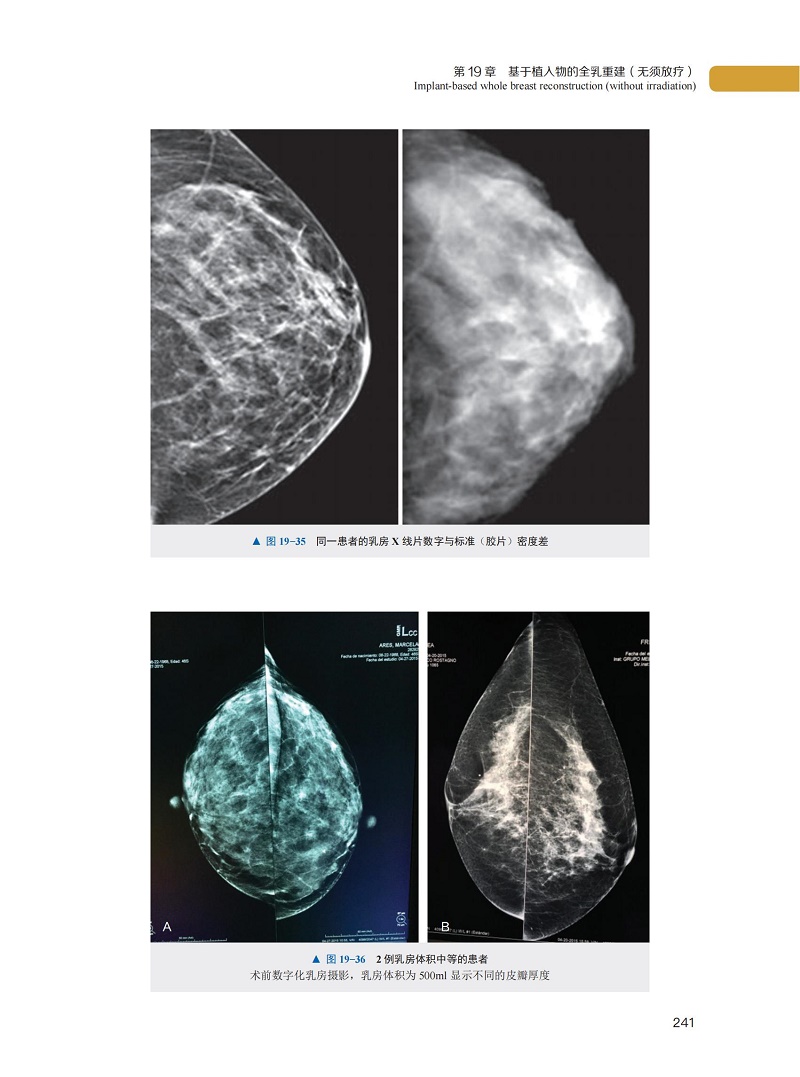

第 19 章 基於植入物的全乳重建(無須放療)

二、全數位化乳房 X 光攝影與數位乳房斷層融合攝影技術的作用